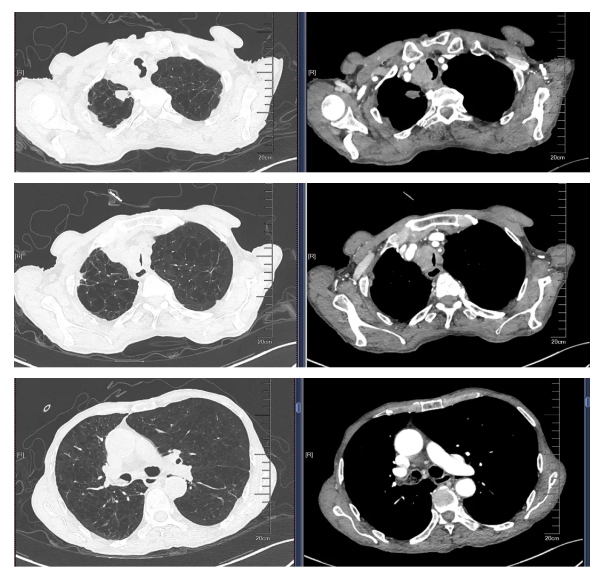

胸外科六病区(胸部肿瘤科)医生王洪涛快速为秦先生完善胸部增强CT(计算机层析成像)检查。结果提示气管右侧见软组织团块影,包绕气管软骨。结合影像学检查结果,王洪涛考虑秦先生为混合型中心气管狭窄,即病变在腔内、腔外均有累及,病变距声门约4厘米,气管病变长度为3.8厘米,最狭窄部位距声门5.7厘米,呈线样,严重程度高于85%。

手术由呼吸内镜中心副主任王振静手术团队操作,体外循环及麻醉团队监测秦先生的生命体征。王振静先用常规支气管镜进行检查,发现气管上段距声门约4厘米处可见新生物,几乎被完全阻塞,上覆黄白苔,镜身(直径4.9毫米)不能通过,后更换硬质支气管镜,进镜顺利,然后快速旋切大部分肿瘤组织。在清除大部分病变组织后,他们在硬质支气管镜直视下顺利植入一枚覆膜支架。